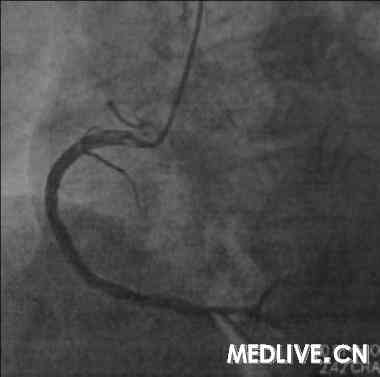

经右股动脉途径,6F,JR4.0引导管,HT BMW Universal引导丝顺利通过右冠闭塞病变部位,Diver血栓抽吸导管于病变部位及其近、远段部位连续抽吸,反复5次,造影可见右冠血流恢复,余狭窄最重部位直接植入Excel支架3.5*14mm,12atm释放,16atm原位后扩张,最重效果满意,右冠TIMI血流3级(图5-7)。

急诊右冠介入治疗成功(图12);择期回旋支的介入治疗成功(图11)。